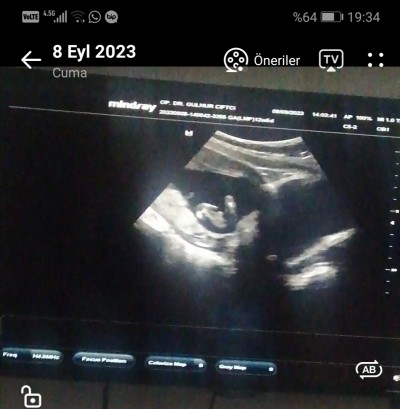

Doktor önce kız dedi sonra erkeğe benziyor dedi daha randevuma 1 buçuk ay sizce nedir?

Gebelik haftası 13+3

Bu erkek kesesinden belli

Canım bilemedim ama ben sana koyayım ultrason eğer sizinde böyleyse erkektir elinizde ultrason kağıdı olduğu için daha iyi bilirsiniz